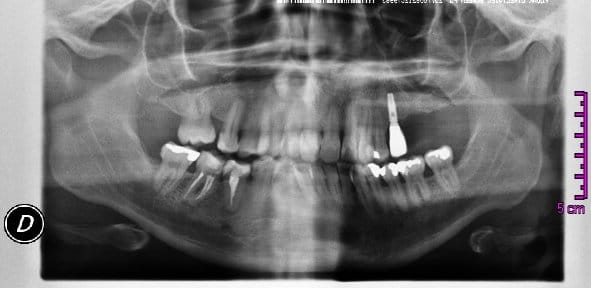

Esta es la mas nueva y es de aproximadamente 2 años despues.